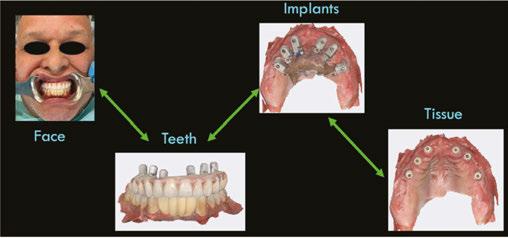

When imported into a design software (e.g., Exocad), the OPTISPLINT scan will produce a digital file of implant positioning. Additional records include facial records, soft tissue records, and tooth/occlusal records (Figure 6).

After all the records are acquired, the scans may then be aligned and the patient’s implant prosthesis can be designed and fabricated (Figures 7A-7F). The OPTISPLINT technique enables clinicians to utilize a fully-digital workflow for a fraction of the cost of other digital methods. Patient factors are able to be eliminated as the OPTISPLINT can be scanned extraorally with the added benefit of acting as a verification jig prior to prosthetic delivery.

Figures 7A-7F: 7A. Alignment of facial record to teeth, to aid in smile design and tooth setup. 7B. Detecting implant position via scan region of OPTISPLINT jig. 7C. Alignment of patient’s teeth to soft tissue, to allow tooth setup at correct vertical dimension. 7D. Alignment of implant position to soft tissue. 7E. Digital design of patient’s prosthesis. 7F. Final prosthetic delivery

Figure 6: Summary of records acquired that will be aligned in CAD software